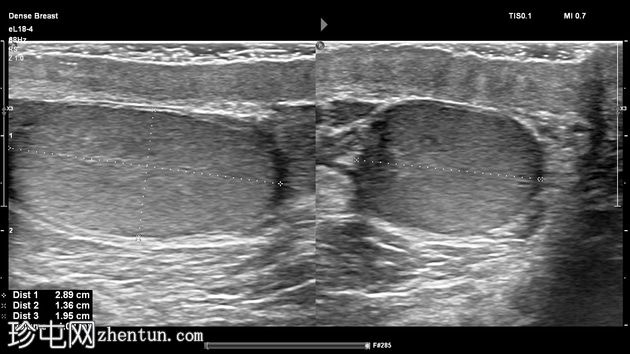

左侧阴囊内可见两个相邻但彼此分离的小睾丸,头侧体积分别为1毫升和3.5毫升,共用一个附睾。

两个睾丸回声和血流均正常,内部未见病变,但患侧可见少量鞘膜积液。